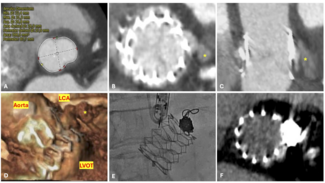

The patient was sent for coronary artery catheterization that was performed via right radial artery approach (6 Fr Glidesheat and 5 Fr Optitorque radial TIG catheter Terumo interventional systems). The angiographic findings were a mild mid left main coronary artery (LMCA) lesion, a partially recanalized chronic left anterior descending (LAD) coronary artery proximal occlusion with excellent collaterals, severe proximal left circumflex (LCX), mid obtuse marginal (OM) stenosis (Figure 1A), and a severe stenosis of the bifurcation compromising the posterior descending and posterolateral branches of the right coronary artery (not shown in figures).

The patient was sent for coronary artery catheterization that was performed via right radial artery approach (6 Fr Glidesheat and 5 Fr Optitorque radial TIG catheter Terumo interventional systems). The angiographic findings were a mild mid left main coronary artery (LMCA) lesion, a partially recanalized chronic left anterior descending (LAD) coronary artery proximal occlusion with excellent collaterals, severe proximal left circumflex (LCX), mid obtuse marginal (OM) stenosis (Figure 1A), and a severe stenosis of the bifurcation compromising the posterior descending and posterolateral branches of the right coronary artery (not shown in figures).

The patient refused coronary artery bypass graft surgery and we therefore performed a percutaneous coronary intervention (PCI) by the radial artery approach. The LMCA was engaged with an EBU 3.5 6 Fr guiding catheter. The LAD occlusion was crossed using a 0.014” Pilot 50 guidewire (Abbott Vascular), and subsequently pre-dilated with a 2.0 mm x 20 mm Maverick (Boston Scientific) in several occasions at 10 atm of pressure, achieving TIMI 2 coronary artery flow. We then deployed 2 overlapping Endeavor Resolute cobalt-chromium drug-eluting stents (DES) (Medtronic Inc.) at 12 atm from distal to proximal, 2.5 mm x 30 mm and 2.75 mm x 24 mm, respectively. During the delivery of the proximal stent, a type B dissection developed within the ostium of the LAD extension and anterograde flow compromise (Figure 1B), which forced us to deploy another ostial 2.75 mm x 18 mm overlapped Endeavor Resolute DES despite the risk of jailing the origin of the LCX. The stent was deployed at 12 atm with good angiographic result re-establishing TIMI 3 flow.

We decided to gain right femoral artery access in order to use a 7 Fr system to improve guiding catheter support, alignment, and to protect the LAD during performance of a certainly difficult procedure. The first angiogram showed the presence of a longitudinal compression of the ostial LAD stent (Figure 2B) probably due to the previous forceful withdrawal of the detached and jammed stent with secondary and involuntary deep guiding catheter intubation. We decided to wire the LCX and the LAD with BMW guidewires and, taking advantage of the longitudinal compression of the LAD stent, we were able to easily advance balloons and stents into the distal segments of the OM (Figure 3A). Then 2 non-overlapped Endeavor Resolute DES (2.5 mm x 18 mm an 2.75 mm x 24 mm) were delivered to the LCX without difficulties, resulting in a good final angiographic result with no further compromise of the ostial LAD stent.

We decided to gain right femoral artery access in order to use a 7 Fr system to improve guiding catheter support, alignment, and to protect the LAD during performance of a certainly difficult procedure. The first angiogram showed the presence of a longitudinal compression of the ostial LAD stent (Figure 2B) probably due to the previous forceful withdrawal of the detached and jammed stent with secondary and involuntary deep guiding catheter intubation. We decided to wire the LCX and the LAD with BMW guidewires and, taking advantage of the longitudinal compression of the LAD stent, we were able to easily advance balloons and stents into the distal segments of the OM (Figure 3A). Then 2 non-overlapped Endeavor Resolute DES (2.5 mm x 18 mm an 2.75 mm x 24 mm) were delivered to the LCX without difficulties, resulting in a good final angiographic result with no further compromise of the ostial LAD stent.